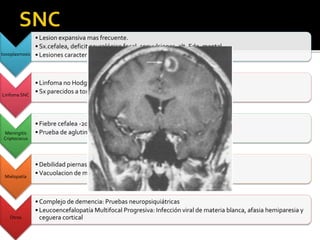

• Lesion expansiva mas frecuente.

• Sx.cefalea, deficit neurológico focal, convulsiones, alt. Edo. mental.

• Lesiones características enTAC

Linfoma SNC

• Linfoma no Hodgkin

• Sx parecidos a toxoplasmosis. Diferenciar:TAC

Meningitis

Criptococus

• Fiebre cefalea -20% meningismo

• Prueba de aglutinación látex +, cultivo,Tinta china

Mielopatía

• Debilidad piernas e incontinencia

• Vacuolacion de materia blanca

Otros

• Complejo de demencia: Pruebas neuropsiquiátricas

• Leucoencefalopatía Multifocal Progresiva: Infección viral de materia blanca, afasia hemiparesia y

ceguera cortical